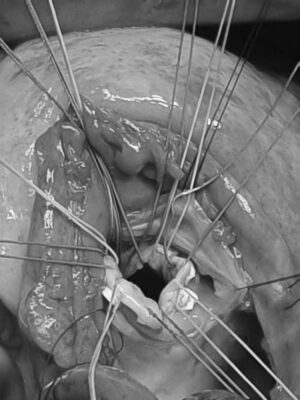

İkinci aşamada, kalp-akciğer makinesine bağlanma işlemi yapılır. Bu makine VSD ameliyatı sırasında vücuda oksijen ve kan pompalar. Üçüncü aşamada, cerrah VSD alanını bulmak için kalbin sağ ve sol karıncıklarını ayıran septuma ulaşır. Cerrah, bozulmanın yerini belirledikten sonra yama veya dikişler kullanır. Bu yamalar genellikle hastanın dokusundan veya biyouyumlu malzemelerden yapılır ve kalbin yapısına uyum sağlar.

- Koltukaltı-sağ atriyumdan vsd kapama

VSD tamiri, kalpteki ventriküler septal defektin açık kalp cerrahisiyle kapatılması şeklinde yapılır. Operasyon sırasında öncelikle hasta genel anestezi altında uyutulur ve göğüs kafesi açılarak kalbe ulaşılır. Kalbin çalışması geçici olarak durdurulur ve bu süreçte kalp-akciğer makinesi kullanılarak dolaşım sağlanır. Defektin boyutuna ve yerine göre sentetik yamalar veya hastanın kendi dokuları kullanılarak açıklık kapatılır. Bu yama işlemi, kalbin sağ ve sol ventrikülleri arasındaki anormal kan akışını durdurmak için gereklidir. Ameliyat sonrası kalbin normal dolaşımı sağlanır ve kalp fonksiyonları düzeltilir. Başarılı bir VSD tamiri sonrası kalpte oluşabilecek komplikasyonların riski önemli ölçüde azalır. İşlemin zamanında yapılması, hastanın uzun vadeli kalp sağlığı ve yaşam kalitesi açısından büyük önem taşır.